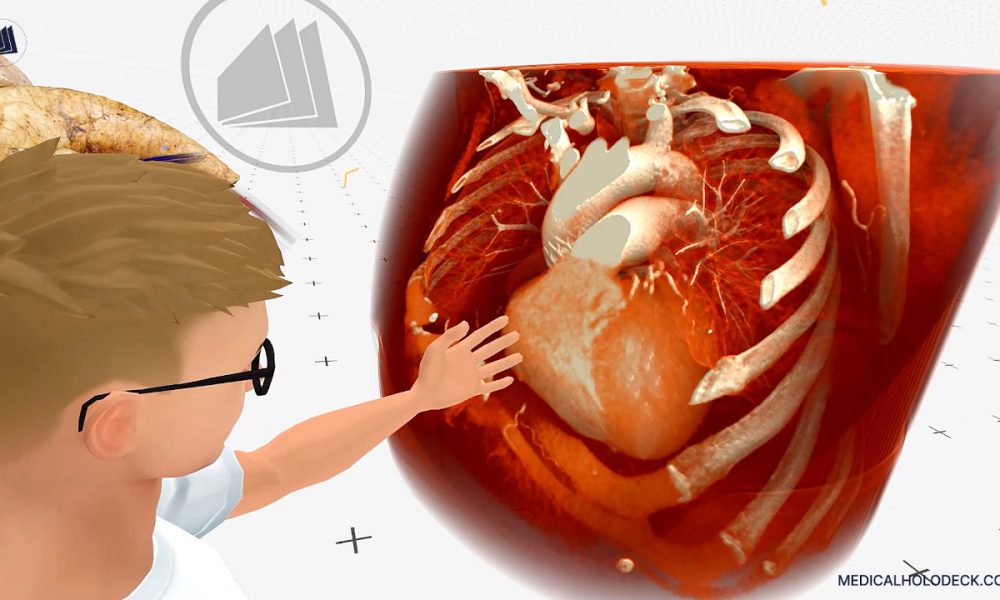

Would you believe this wasn’t shot on a real…